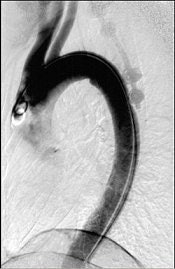

"This patient arrived at the ER paraplegic. We see a little compression here, but we cannot see the entire problem. When we do CT, we see that this is a huge burst fracture. This was fairly acute. (The surgeon) did a corpectomy, which we followed with CT. He put a graft, two levels above and below the fusion," El-Khoury said. "When we looked closely at the CT, we noticed that the lower two screws are sitting and indenting the aorta. We called the surgeon and told him this: 'You have a situation in which you have metal screws pulsating against an aorta, and you know who is going to win in the end.' So the surgeon did an angiogram. The surgeon went in, removed the screws, and fused the patient from the back."